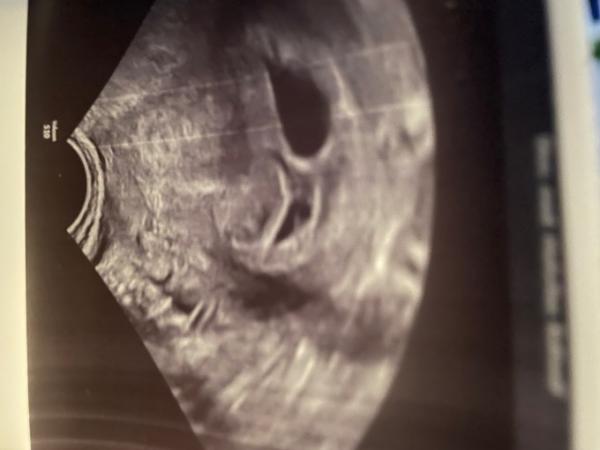

Hallo, ich hatte heut morgen meine erste US, rein rechnerisch bin ich bei 5+3. ES war am 9.12. Allerdings hat mich der Arzt arg verunsichert und mittlerweile denke ich eher, dass es ein windei wird. Er hat beim US sofort eine Fruchthöhle gesehen und hat geschallt und geschallt, aber sie war leer. Da wurde mir schon mulmig. Dann meinte er aber das da noch was 2. sei, man aber nichts erkennen könne. Ich solle in einer Woche wiederkommen. Ingesamt hat er mir wenig Hoffnung gemacht. Man hätte wohl schon mehr sehen müssen. Mich würde eure Meinung Interessen. ET wäre übrigens Ende August gewesen

Liebe Mason95, mir ging es bis gestern 2 Wochen lang wie dir. Bei 5+2 war nur eine leere Fruchthöhle zu sehen. Nicht mal der Ansatz eines Dottersacks. Da ich den Befruchtungszeitpunkt aufgrund meiner künstlichen Befruchtung genau kannte, war ich mir sicher, dass es schief geht. Gestern (7+1) war ich wieder beim Ultraschall. Dort wurden zwei Embryos mit Herzschlag festgestellt, die zeitgerecht entwickelt sind. Ich hoffe das macht dir etwas Mut.